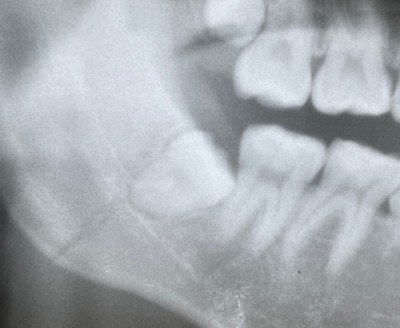

10才で永久歯(6才臼歯)を抜歯した症例の5年経過